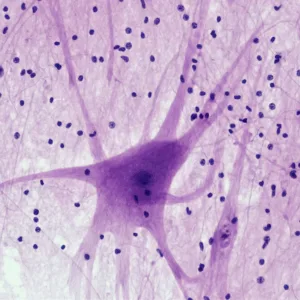

¿Tienes antecedentes familiares de Parkinson? ¿Comienzas a notar temblores leves, rigidez o dificultad de concentración? La enfermedad de Parkinson puede desarrollarse de forma silenciosa durante años. El Perfil Genético Parkinson te permite conocer tu riesgo personal a través de una simple muestra de saliva, ayudándote a actuar antes de que aparezcan los síntomas clínicos.

Este análisis genético de saliva estudia 21 genes clave relacionados con la aparición y progresión del Parkinson. Mediante tecnología de genotipado de alta precisión, se identifican variantes implicadas en: